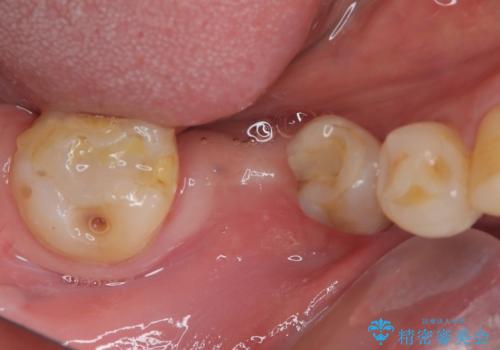

奥歯がしみる オールセラミッククラウンによる奥歯のむし歯治療